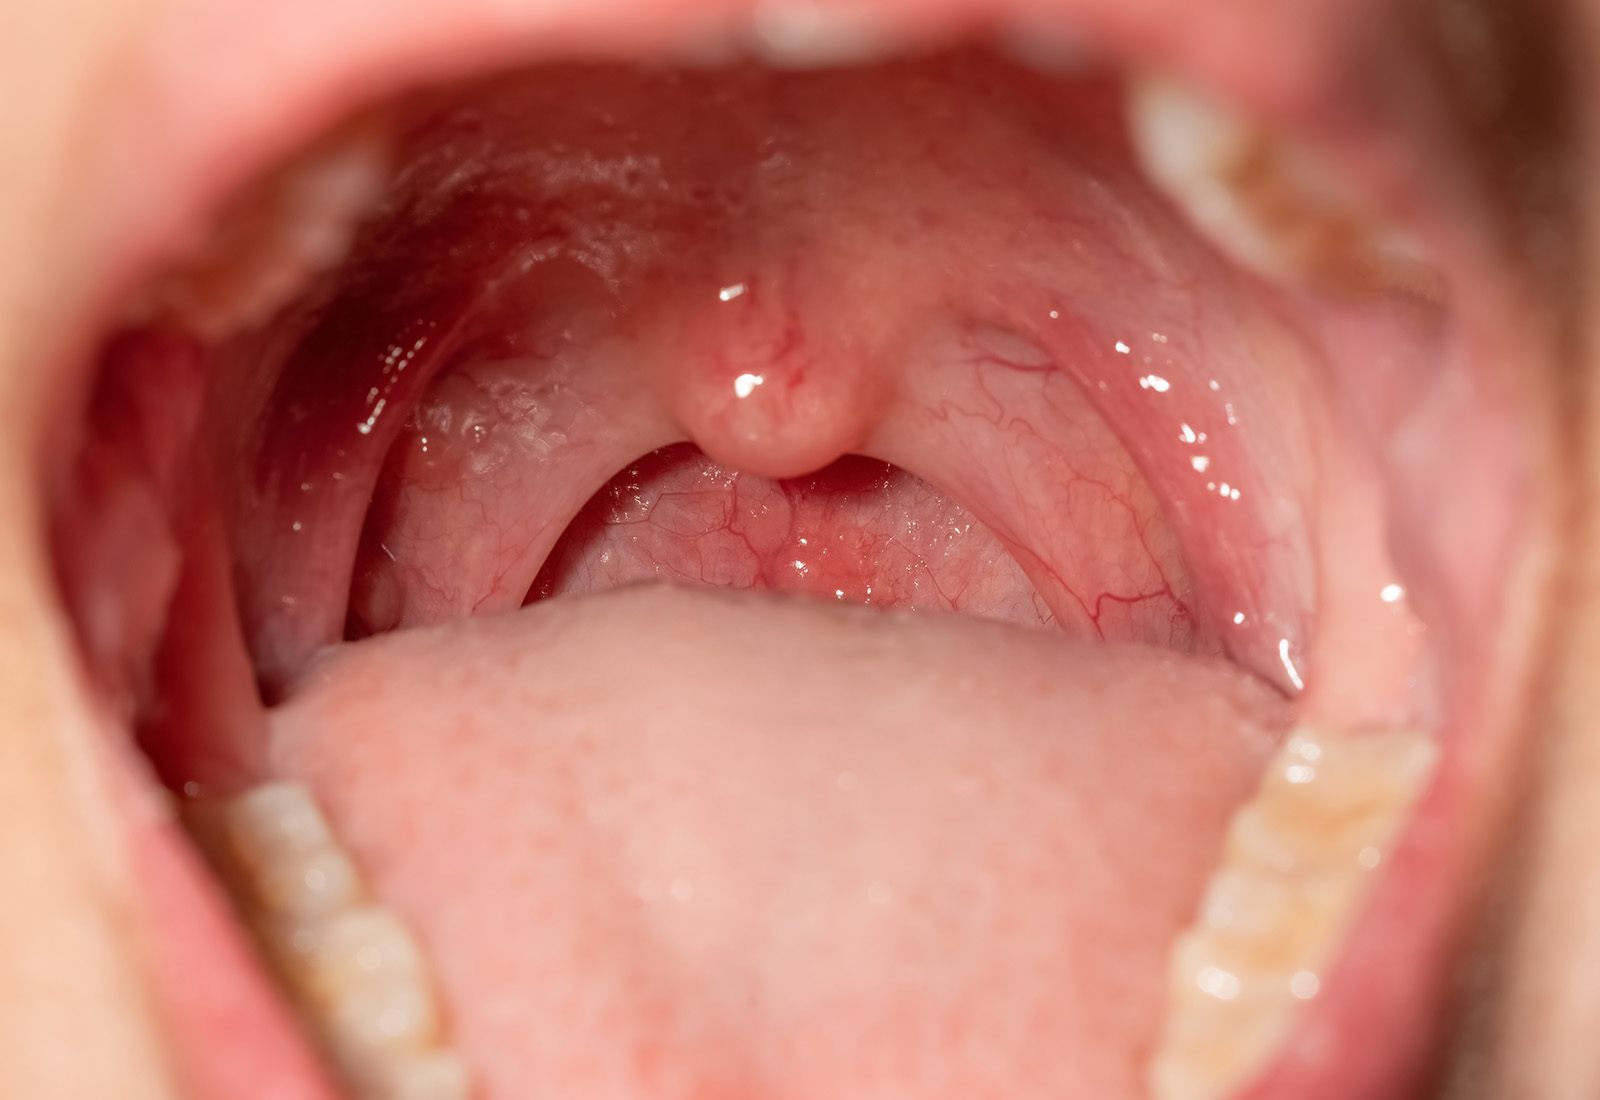

Mengenal Tonsilektomi, Operasi Pengangkatan Amandel yang Bengkak dan Meradang

Tonsilektomi adalah operasi pengangkatan amandel yang bengkak akibat meradang secara berulang. Untuk lebih jelasnya, simak informasi seputar tonsilektomi di sini!